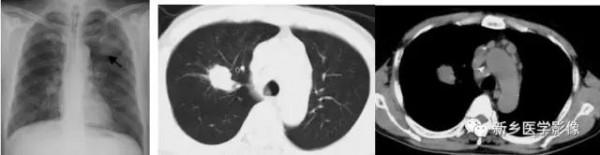

肺部腫塊X線胸部正位、CT圖;a、X線胸部正位片示左上肺腫塊(↑);b和c、胸部CT肺窗和縱隔窗示右上肺腫塊,縱隔淋巴結腫大

左肺結核球X線胸部正位片、CT縱隔窗圖;a、X線胸部正位片;b、CT縱隔窗示鈣化(↑)